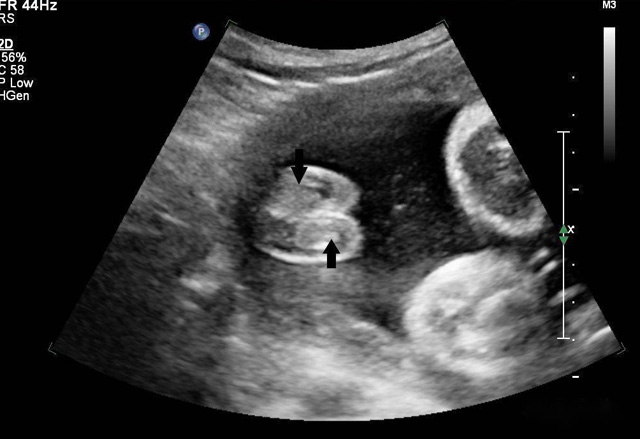

三维超声技术可用于心脏、腹腔、妇科、产科、小器官、血栓、血管成像等多方面。